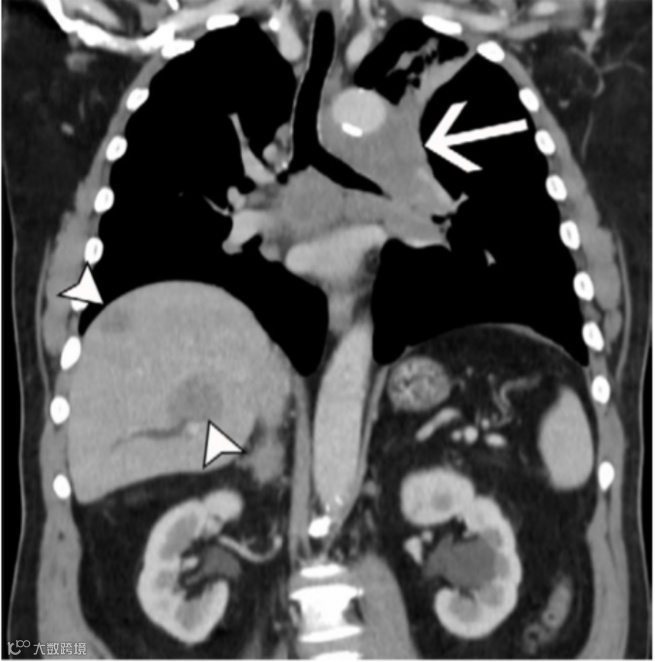

图15. 64岁男性非小细胞肺癌(NSCLC)患者的M1c1期转移性病变。

增强胸部CT扫描的冠状重建图像(软组织窗)显示左上叶肿块(箭头)侵犯纵隔,并且仅在肝脏内发现多个转移灶(短箭头)。